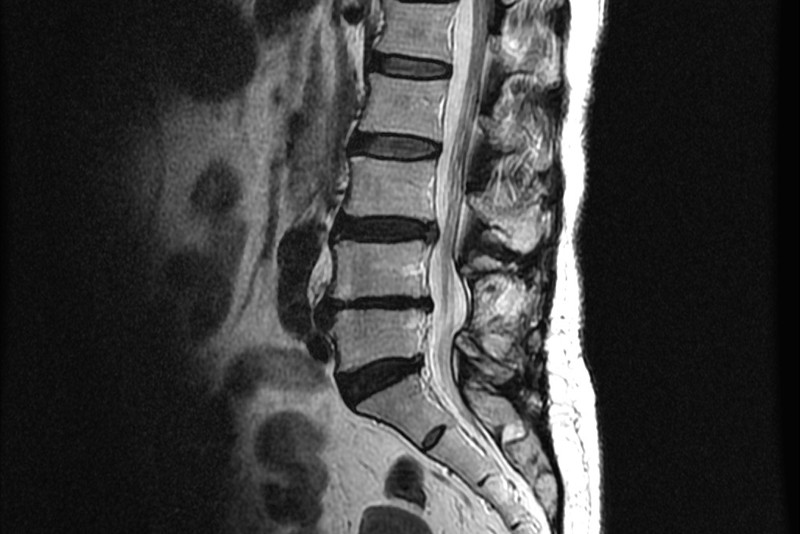

척추와 뼈 사이에 위치한 이 디스크는 외부로부터의 물리적 충격을 완화하고 단단한 뼈가 직접 충돌할 때 문제가 발생하지 않도록 하는 탄성이 높은 구조입니다. 외부의 영향이나 잘못된 위치로 인해 디스크가 꺼지면 염증이 발생하고 신경이 눌려 요통과 요통이 발생합니다. 기술적으로는 요추 디스크 분리라고 하며 일반적으로 요추 디스크 고장이라고 합니다.